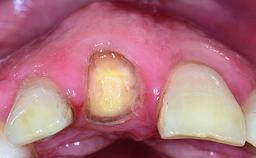

A 36-year-old male patient with a compromised maxillary central incisor was referred by his general dentist for consultation. The patient’s chief complaints were the gradual debonding of a temporary crown on the right central incisor and unsatisfactory esthetics due to an increasing diastema between the right central and lateral incisors. The patient reported a traumatic event some years previously, when a crown had been placed after root-canal treatment. The referring dentist wanted to provide a new crown restoration, but was concerned about the condition of the residual root. Anamnesis was negative for any other dental or periodontal pathology in the remaining dentition. The patient reported taking no medications: He was a smoker (10 to 15 cigs/day) and had realistic esthetic expectations.

Bone Volume Deficient horizontally, requiring prior grafting

Soft Tissue Contour and Volume Slightly compromised